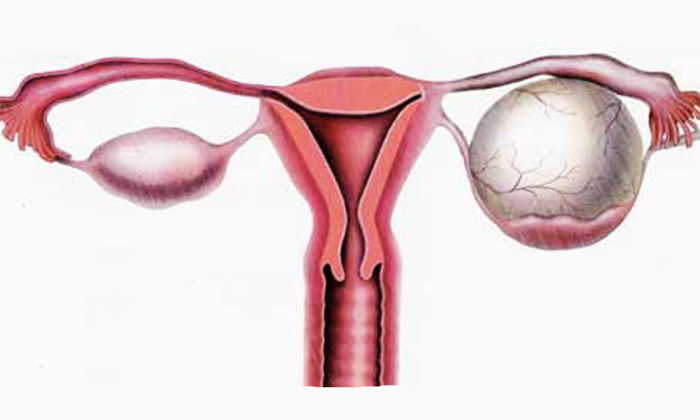

— Yumurtalıklarda kist oluşumu ; polikistik over sendromlu hastaların

yumurtalıkları çok sayıda içi sıvı dolu kesecikle doludur.Buna bağlı olarak ta

yumurtalıklar,normalin 2-3 katına kadar büyürler.